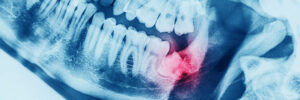

X-ray oral image with an inflamed wisdom tooth

One of the most common questions we hear from patients is whether removing wisdom teeth is truly necessary. While every smile is unique, understanding how wisdom teeth develop, and the problems they can potentially cause, can help you make an informed, confident decision about your oral health. Why Wisdom Teeth Can Become a Problem Wisdom… Read more »